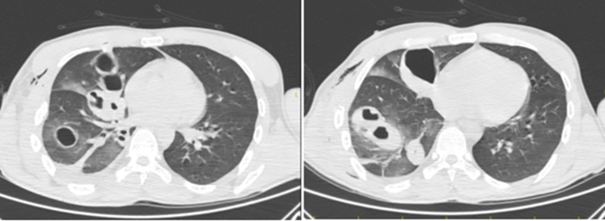

A 34-year-old male patient presented to the emergency department following a motorcycle accident resulting in multitrauma. Despite an unstable general condition, vital signs remained stable. The patient underwent multidisciplinary evaluation, revealing liver and spleen injuries, right hemopneumothorax, diffuse subcutaneous emphysema, and large traumatic cysts in the right lung (Figure 1). Additionally, fractures of the right 4th, 5th, 6th, and 7th ribs, right scapula, proximal humerus, and right olecranon avulsion fracture were identified through imaging studies. Immediate right tube thoracostomy was performed in the emergency room, followed by surgical intervention by the general surgery team and completion of orthopedic treatments. Subsequent to tube thoracostomy, due to minimal drainage, absence of significant air leakage, and radiographic confirmation of lung expansion within the right hemithorax, a decision was made for conservative management with close observation. Following approximately two weeks of intensive care unit monitoring, the patient was transferred to the ward. Chest tube removal was conducted in the ward, and the patient was monitored for an additional hour. Sequential posteroanterior (PA) chest radiographs taken at regular intervals revealed a reduction in size of the giant cysts with fluid accumulation. Upon stabilization of clinical status, the patient was discharged. Subsequent outpatient clinic evaluation two months later demonstrated regression of the giant cysts on thoracic CT imaging (Figure 2A–2C).

Figure 1 Posttraumatic thorax CT and traumatic pulmonary pseudocysts.

2C Thorax CT taken at the 2nd month.